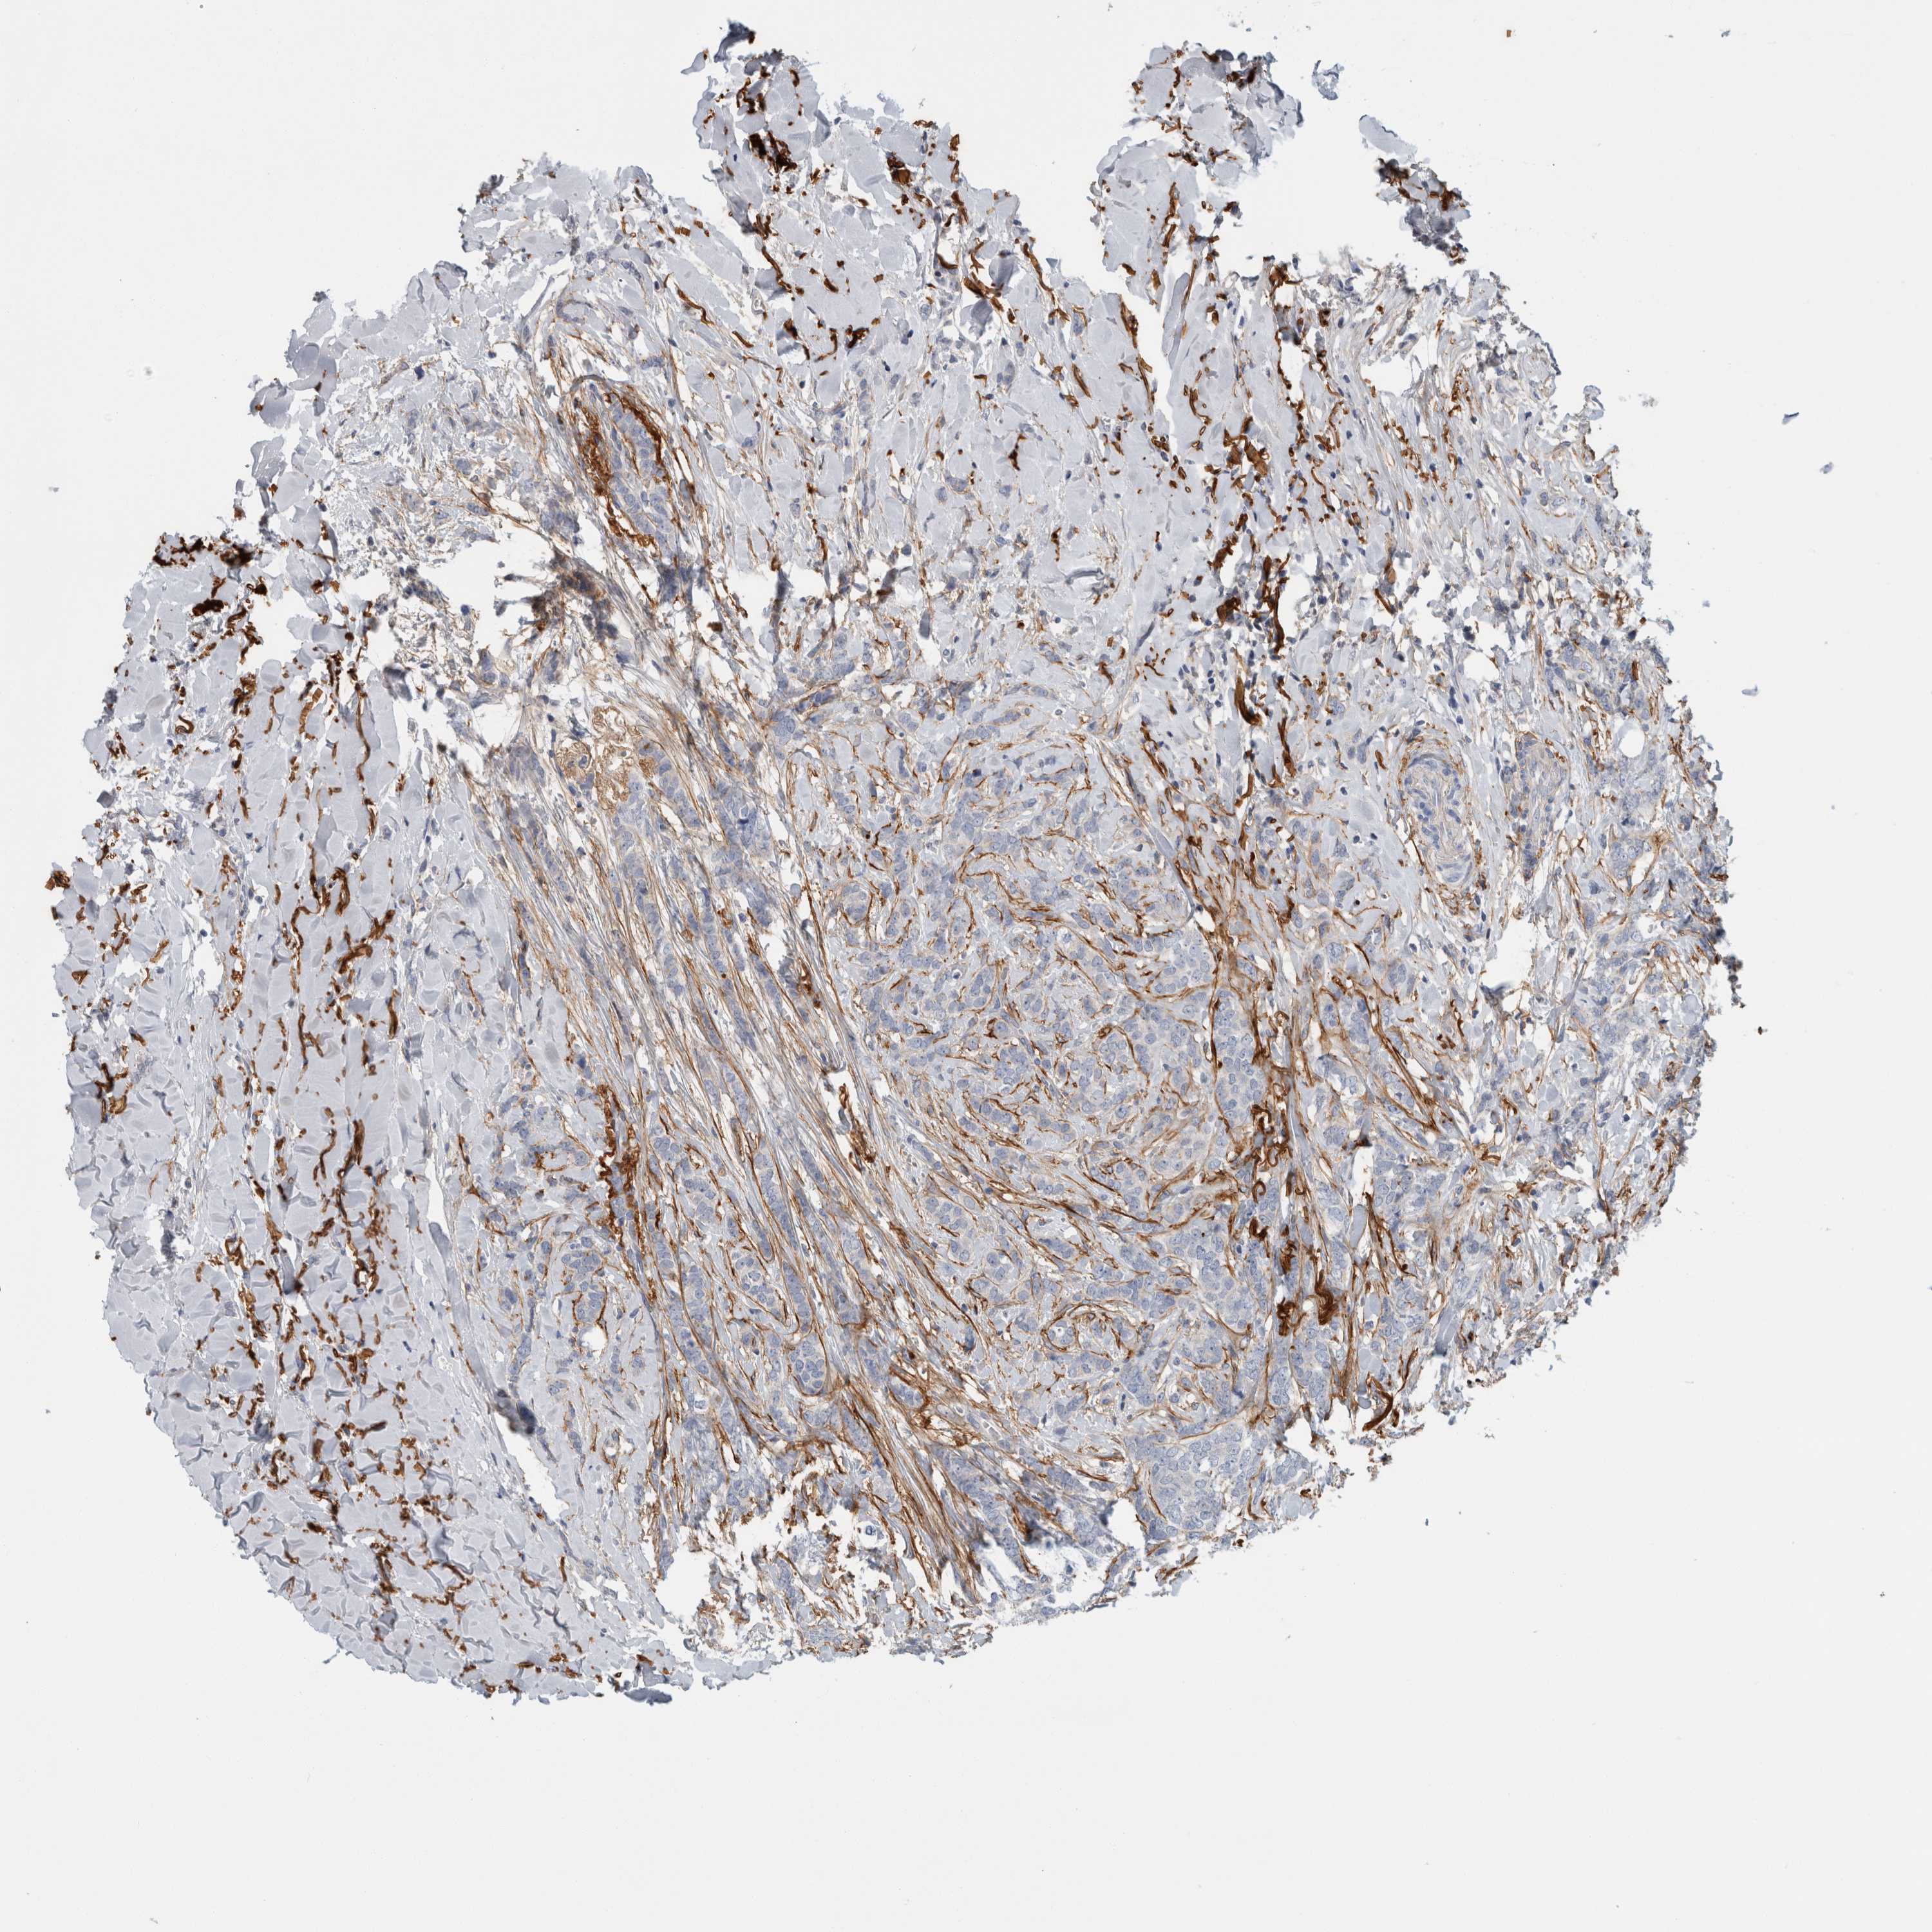

BRCA TCGA BRCA VALIDATION PROTEIN EXPRESSION

ANTIBODIES

AND

VALIDATION